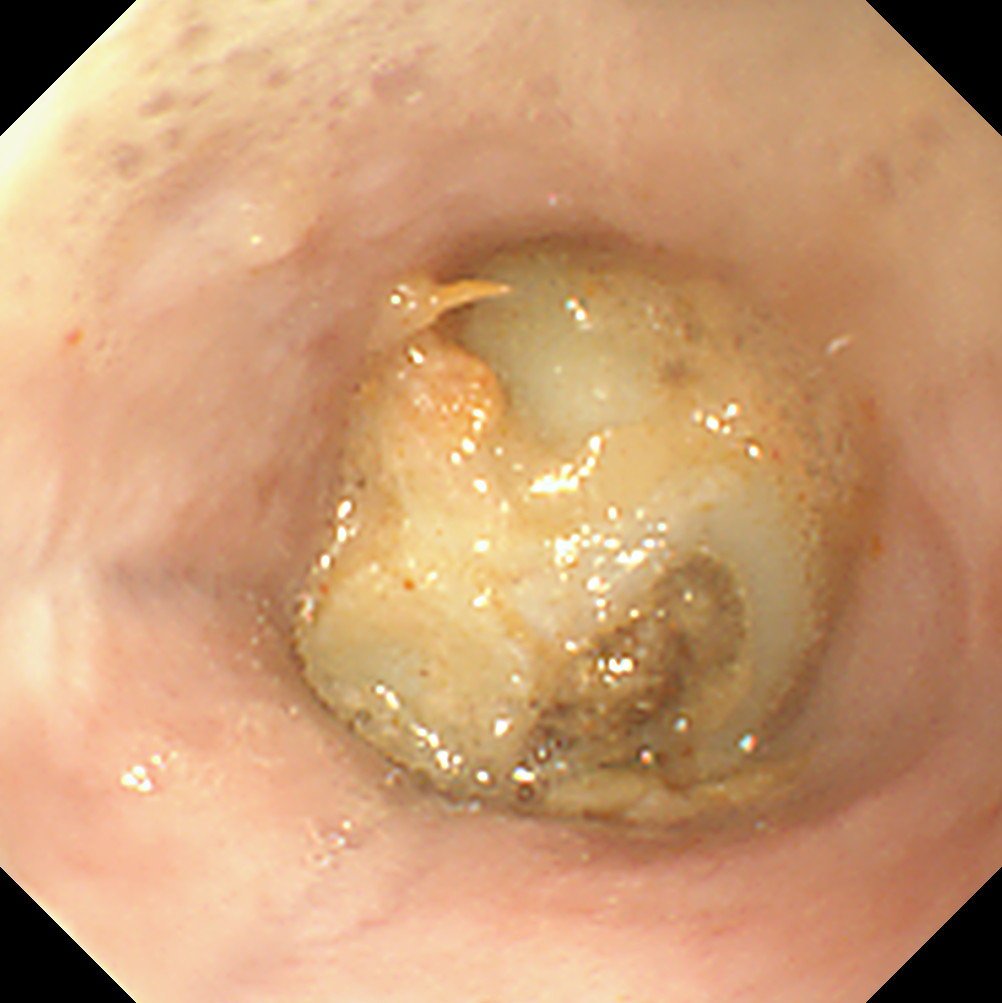

Other gastric FBs are simply too large to retrieve, either because they cannot be grasped or they are too large to pull back through the lower oesophageal sphincter (LOS) even though the patient managed to swallow them (Figure 2). Indeed, the availability and size of grasping instruments restrict the range of FBs that can be retrieved endoscopically. Unless the endoscope has a large channel (preferably 2.8mm), many instruments cannot be passed. However the large channel results in a larger endoscope tip diameter, precluding some attempts in small dogs and cats.